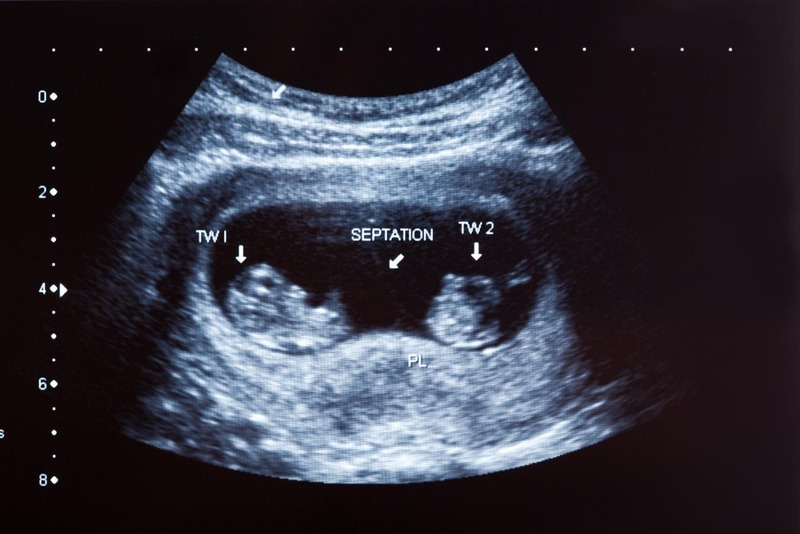

Siêu âm hoàn toàn có thể phát hiện thai đôi và là phương pháp chẩn đoán chính xác nhất hiện nay. Từ tuần thai thứ 6–8, siêu âm đầu dò âm đạo hoặc siêu âm bụng có thể thấy rõ hai túi thai hoặc hai phôi thai trong tử cung. Bác sĩ cũng có thể xác định thai đôi cùng trứng (chung nhau thai) hay khác trứng (hai nhau thai riêng biệt), điều này rất quan trọng để theo dõi các nguy cơ trong thai kỳ. Ngoài việc đếm số thai, siêu âm còn giúp kiểm tra sự phát triển của từng thai, tình trạng nhau thai và lượng nước ối. Nhờ vậy, thai phụ mang song thai được chăm sóc và theo dõi sát sao hơn để phòng ngừa biến chứng.

Siêu âm có thể phát hiện thai đôi khá sớm, thường từ tuần thứ 6–8 của thai kỳ. Ở giai đoạn này, siêu âm đầu dò âm đạo giúp nhìn thấy rõ hai túi thai hoặc hai phôi thai trong tử cung. Với siêu âm bụng, thai đôi có thể được phát hiện muộn hơn một chút, khoảng tuần thứ 8–10 khi hai túi thai đã phát triển rõ ràng. Ngoài ra, siêu âm trong 3 tháng đầu cũng giúp xác định thai đôi cùng trứng hay khác trứng. Nếu siêu âm quá sớm (trước tuần 5), hình ảnh thai đôi có thể chưa rõ ràng nên cần theo dõi thêm.

- Tuần 6–8: Siêu âm đầu dò hoặc siêu âm bụng để xác định số túi thai, số phôi và tim thai.